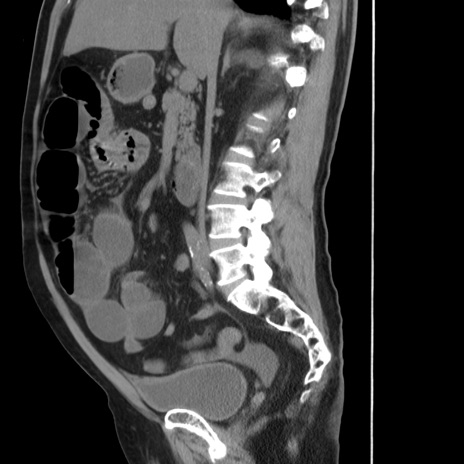

症例20(矢状断像)

【症例】 60歳代男性

【主訴】 腹部膨満、嘔吐

【現病歴】5日前頃より倦怠感を認め食事量減少し4日前の朝嘔吐、食事摂取困難となった。 3日前近医受診し点滴施行され整腸剤などを処方された。 当日他院を受診し、腹部膨満著明、炎症反応の上昇(CRP10.8、WBC11200)あり、紹介受診となる。

【身体所見】 意識JCS1 受け答えがはっきりしないBP 111/57mHg、 P 67bpm、、BT35.2°C、SpO2 97%(RA)、 腹部:膨隆、打診で鼓音あり、全体的に圧痛有り、腸蠕動音(-)、反跳痛ははっきりせず。

【データ】WBC 11400、CRP 14.20